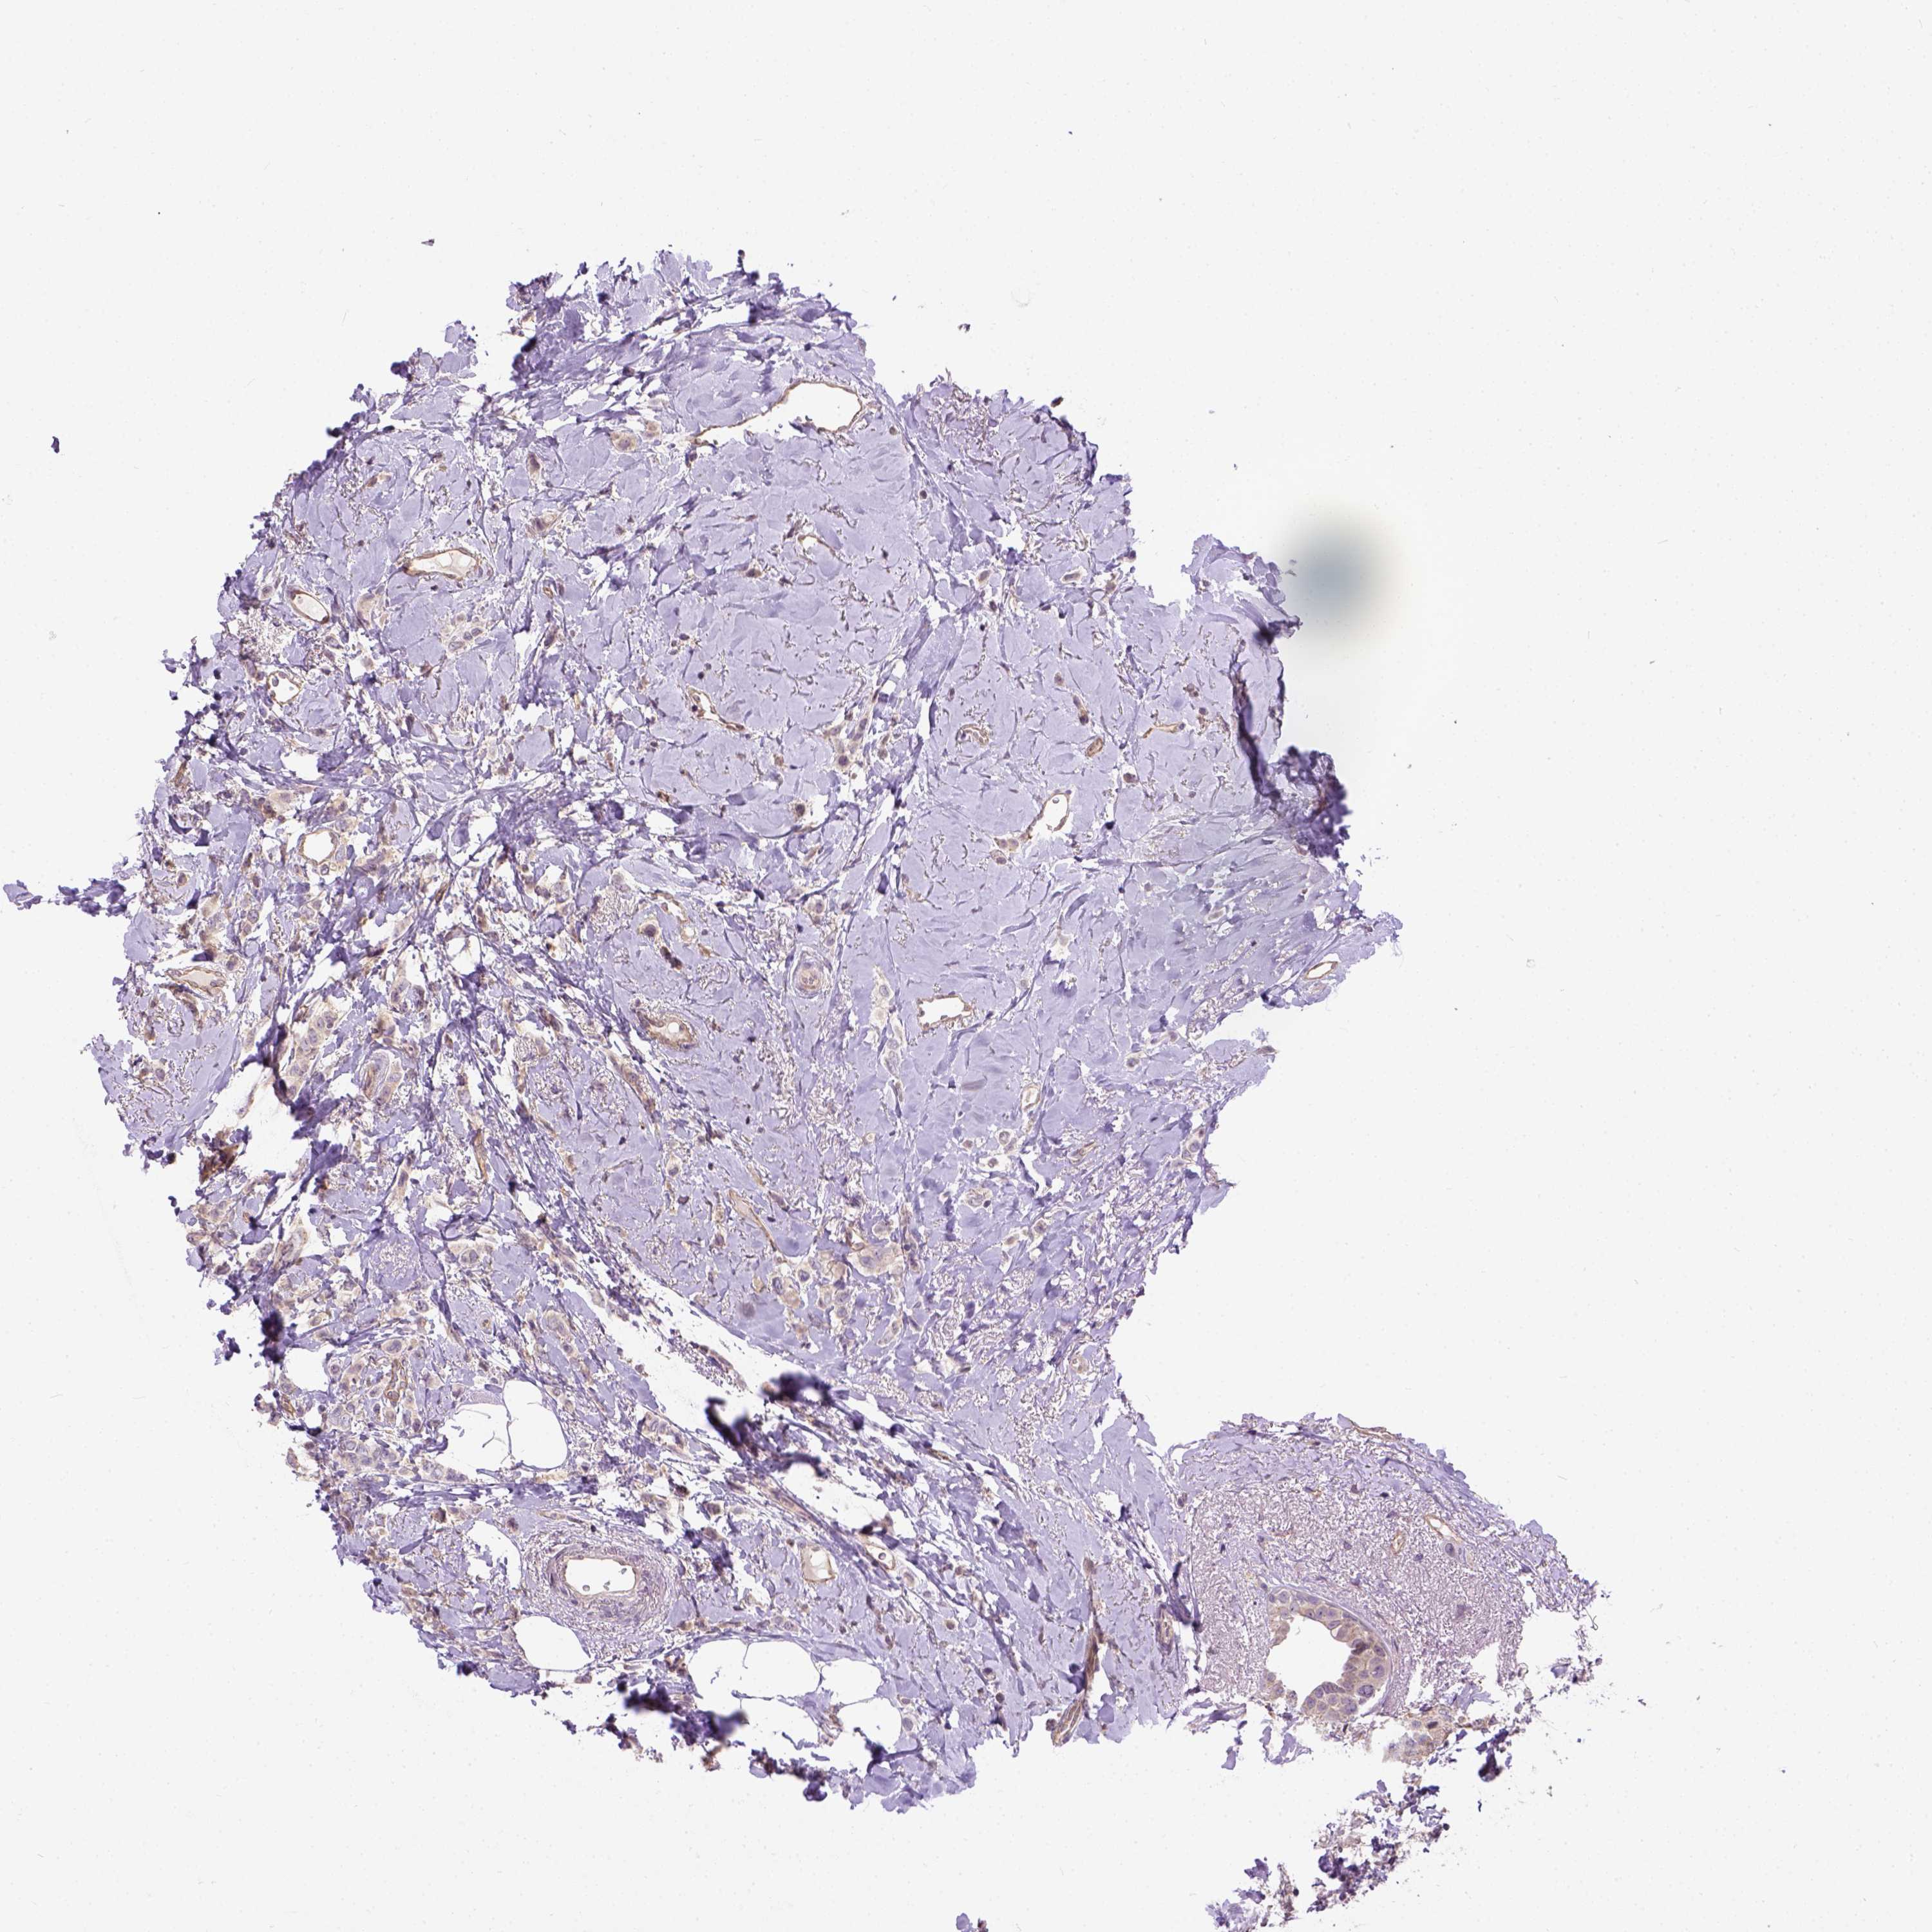

CANCER BREAST CANCER Show tissue menu

BRCA TCGA BRCA VALIDATION PROTEIN EXPRESSION

Breast cancer

Human cancer